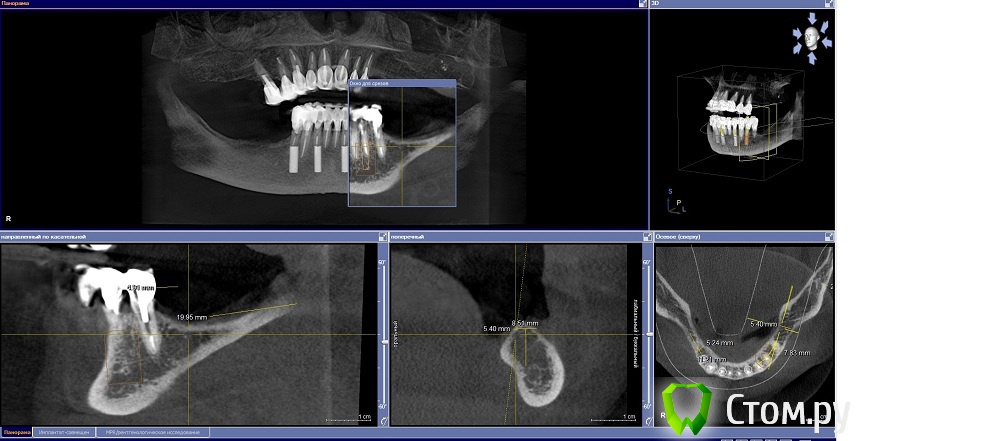

Dr.Sham Опубликовано 14 октября, 2014 Поделиться Опубликовано 14 октября, 2014 (изменено) Планируется удаление всех зубов на НЧ. Пациентка хочет несъемную конструкцию.Вот нарезка.Планируется имплантация Ankylos в позициях 46, 44, 42, 32, 34, 36.В боковых отделах дефицит всего.Думаю удалить зубы через один, чтобы на них временная конструкция держалась, а в промежутках имплантаты.В переднем отделе узко, либо узкие ФДМки, либо заглушка и в овоид край времянок или закрыть свободным трансплантатом.Что думаете?В боковых отделах вопрос...короткие имплантаты и НКР? От сложной костной пластики пациентка отказывается категирочески. Сверху пациентка так же хочет несъем. Поэтому все на 4-х, наверное, не самамя удачная конструкция здесь. Зубы сохранить никак, преп под десной местами по 3 мм. ну и дентин весь мягкий. Изменено 14 октября, 2014 пользователем Dr.Sham Ссылка на комментарий

Dr.Sham Опубликовано 14 октября, 2014 Автор Поделиться Опубликовано 14 октября, 2014 Длина винтов при этом играет значение, т.е. 11.5 достаточно или 14 нужны? Ссылка на комментарий

Дмитрий Никитюк Опубликовано 14 октября, 2014 Поделиться Опубликовано 14 октября, 2014 Длина винтов при этом играет значение, т.е. 11.5 достаточно или 14 нужны? Те, которые под углом желательно 14, но можно и 11, а те, которые во фронте можно и меньше, хоть 8.Не забудьте спилить по высоте гребень, если пойдёте по этому пути. Ссылка на комментарий